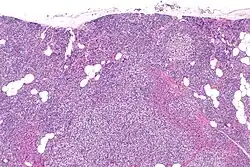

Primary hyperplasia of the parathyroid gland, results from both hypocalcaemia and increased phosphate levels by decreasing expression of calcium sensing receptors and vitamin D receptors at the parathyroid gland.[8][4] These decreases in receptor expression lead to hyperfunctioning of the parathyroid. Hyperfunction of the parathyroid gland is thought to exacerbate primary hyperplasia which evolves further to a secondary more aggressive hyperplasia. Histologically, these hyperplasic glands can be either diffuse or nodular.[24] Primary hyperplasia, usually resulting in diffuse polyclonal growth is manly related to reversible secondary hyperparathyroidism. Secondary hyperplasia of the parathyroid gland is more often a nodular, monoclonal growth that sustains secondary hyperparathyroidism and is the catalyst in the progression to tertiary hyperparathyroidism. Nodular hyperplastic glands in tertiary hyperparathyroidism are distinctly larger in both absolute size and weight up to 20-40-fold increases have been reported.[25][26][24]

Parathyroid glands are normally composed of chief cells, adipocytes and scattered oxyphil cells.[27][14] Chief cells are thought to be responsible for the production, storage and secretion of parathyroid hormone. These cells appear light and dark with a prominent Golgi body and endoplasmic reticulum. In electron micrographs, secretory vesicles can be seen in and around the Golgi and at the cell membrane. These cells also contain prominent cytoplasmic adipose.[27][14] Upon onset of hyperplasia these cells are described as having a nodular pattern with enlargement of protein synthesis machinery such as the endoplasmic reticulum and Golgi. Increased secretory vesicles are seen and decreased intercellular fat is characteristic.[27][24] Oxyphil cells also appear hyperplasic however, these cells are much less prominent.

Biochemically, there are changes in function between normal and nodular hyperplastic parathyroid glands. These changes involve proto-oncogene expression and activation of proliferative pathways while inactivating apoptotic pathways.[28] In nodular parathyroid tissue increased expression of TGF-a, a growth factor, and EGFR, its receptor, results in aggressive proliferation and further downregulation of vitamin D receptors, which act to suppress hormone secretions.[25][8][28] Furthermore, the proliferative marker, Ki67 is seen to be highly expressed in the secondary nodular hyperplastic state.[28][25] Tumour suppressor genes have also been highlighted as being silenced or degraded in nodular hyperplastic parathyroid tissue.[8][28] One such gene, p53, has been shown to regulate multiple tumour suppressor pathways and in tumorigenesis can be degraded by b-catenin. This pathway, in some aspect, is mediated by CACYBP, which is highly expressed in nodular parathyroid hyperplasia.[28]